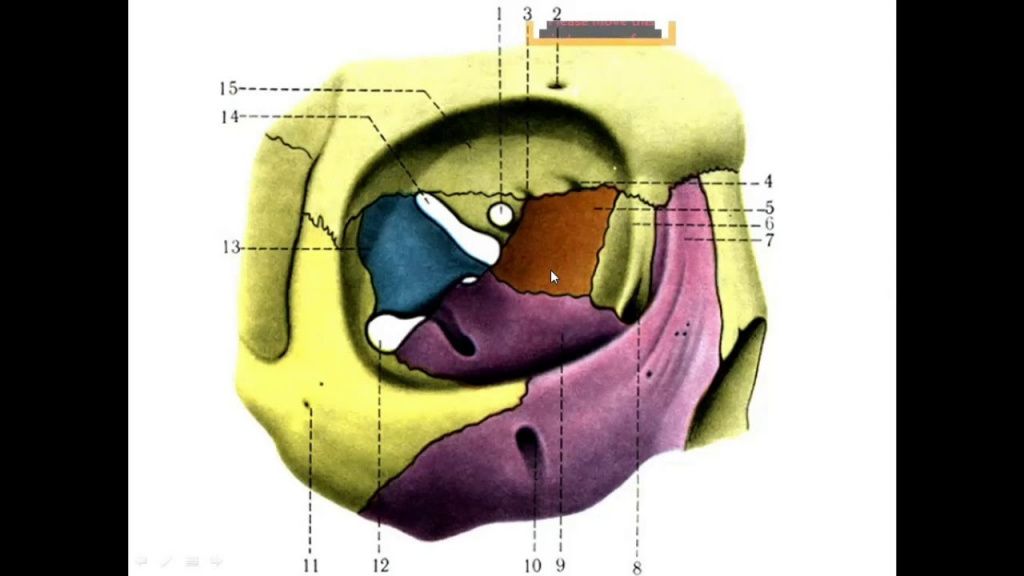

Глазница или глазная орбита представляет собой пространство в форме пирамиды, образованное семью костями. Крыша орбиты состоит из лобной кости и малого крыла клиновидной кости. Боковая стенка орбиты состоит из скуловой кости и большого крыла клиновидной кости. Дно состоит из верхнечелюстной, небной и скуловой костей. Медиальная стенка состоит из решетчатой, верхнечелюстной, слезной костей и малого крыла клиновидной кости.

Глазница или глазная орбита представляет собой пространство в форме пирамиды, образованное семью костями. Крыша орбиты состоит из лобной кости и малого крыла клиновидной кости. Боковая стенка орбиты состоит из скуловой кости и большого крыла клиновидной кости. Дно состоит из верхнечелюстной, небной и скуловой костей. Медиальная стенка состоит из решетчатой, верхнечелюстной, слезной костей и малого крыла клиновидной кости. Медиальная и нижняя стенки орбиты самые тонкие и наиболее подвержены перелому после травмы лица.

В глазной орбите содержится глазное яблоко. Внешняя оболочка глазного яблока состоит из склеры сзади и роговицы спереди. Внутри внешней оболочки находится увеальный тракт, который включает в себя цилиарное тело и сосудистую оболочку. Самый внутренний слой — это нейросенсорная сетчатка, которая может отсоединиться после травмы.